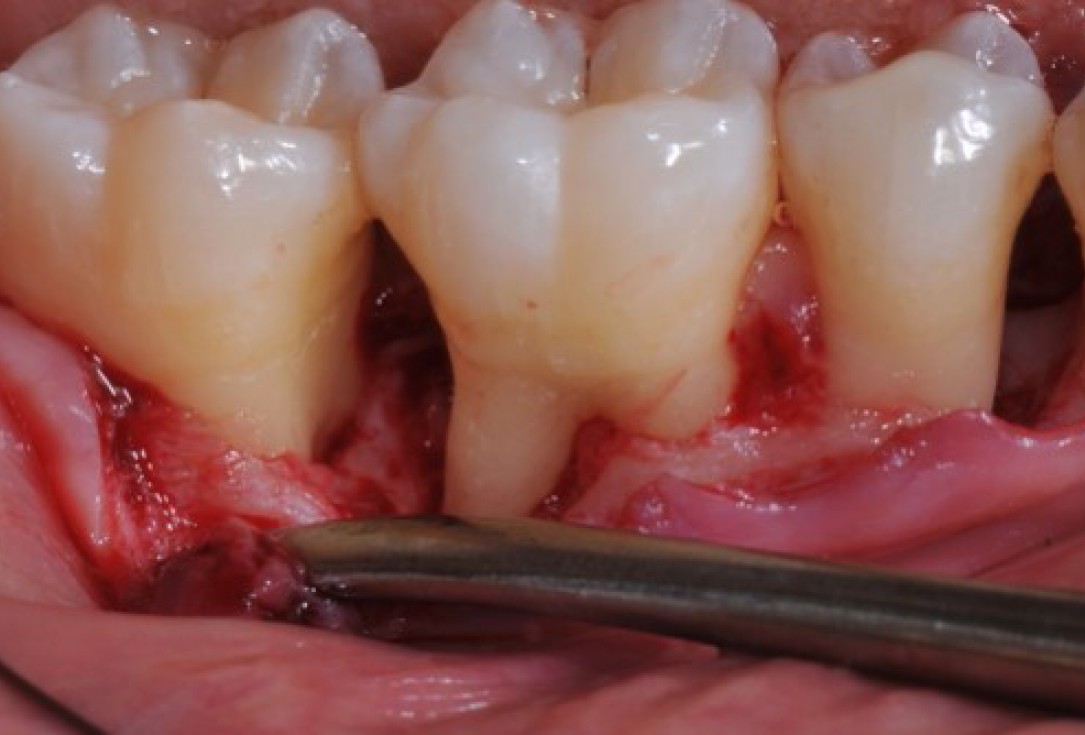

07/22 - Intra-operative view reveals deep non-contained intrabony defects distally to tooth 46 (PPD 10 mm) and on the mesial aspect of tooth 45 (PPD 6 mm). Buccal view.

Deep intrabony defects treated using Straumann® Emdogain® - Dr. M. Stefanini